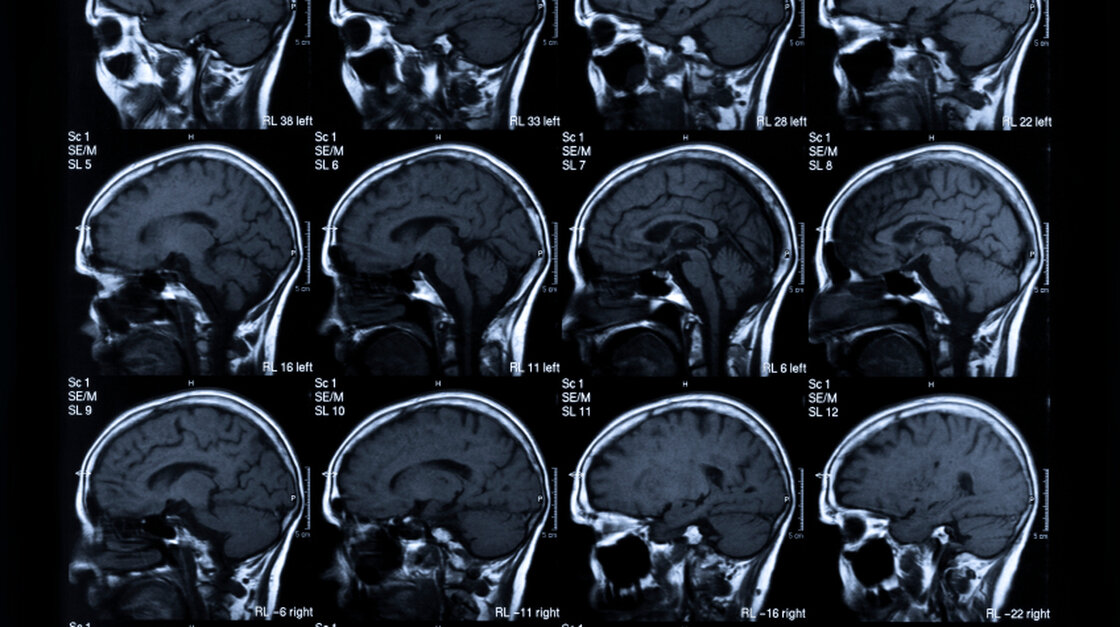

The main goal in stroke treatment: saving brain.

There are a patient history to be taken, lab tests to be run and a brain imaging study to be done. Doctors have to be sure that the patient doesn't have a , where a blood vessel bursts and bleeds into the brain. Using clotbusting drugs on those people can cause catastrophic bleeding. Ischemic strokes, in which a clot blocks blood flow, are more common and are treated with , a drug that is given intravenously to dissolve clots.